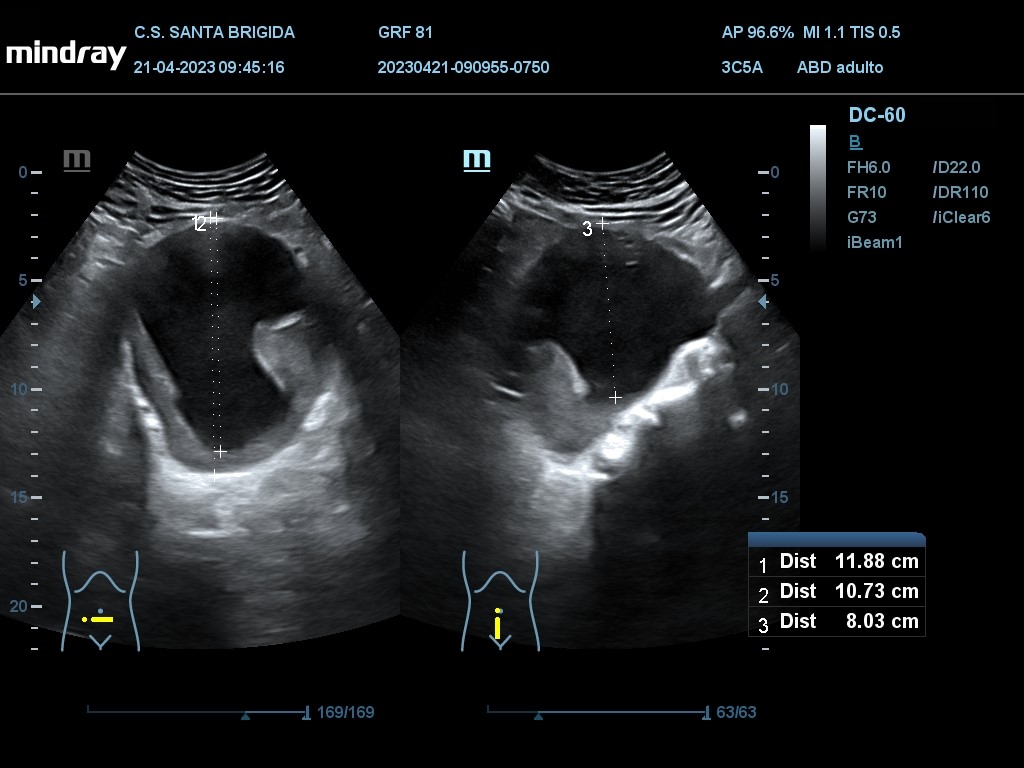

En ecografía clínica se aprecia dilatación de aorta abdominal de extensión máxima de 13,27 cm con origen proximal a la bifuración de las arterias renales y con un diámetro máximo de 9,91 cm. Además asocia imagen hiperecogénica respecto a la luz del vaso en la práctica totalidad de su recorrido en probable relación con trombo intramural semilunar de 3,7 cm.

TAC Abdomen: Voluminoso aneurisma fusiforme de aorta abdominal infrarrenal, de una extensión máxima de 13,8 cm con origen proximal a 3 cm de la bifuración de las arterias renales y punto distal adyacente a la bifurcación de las ilíacas; con un diámetro máximo de 10,6 cm, este asocia un trombo intramural semilunar excéntrico en la práctica totalidad de su recorrido de morfología irregular con un grosor máximo de hasta 3,7 cm. No se objetivan puntos de extravasación de contraste, complicación ni signos sugestivos de rotura inminente (no se objetivan hematomas, soluciones de continuidad, borramiento/acabalgamiento de la pared aórtica posterior sobre vértebra, úlceras penetrantes ni calcio tangencial). No se objetivan alteraciones estructurales en aorta torácica (flaps, aneurismas ni trombos).